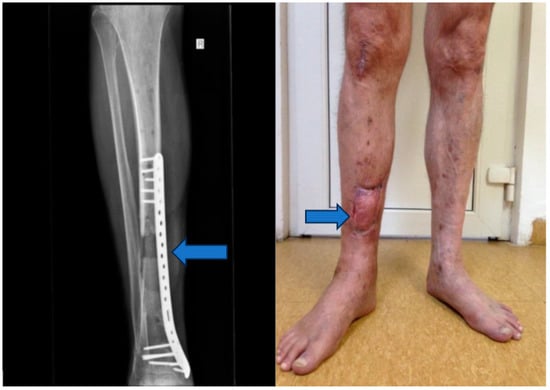

Stage 2: Infection control and debridement (Figure 4).

Objective: To address complications, prevent infection, and manage the wound dehiscence.

Methods: Implants from the initial surgery were removed, wide excisional debridement of necrotic tissue was carried out, pulse lavage was performed for wound cleansing, and osteoclasia was executed to facilitate bone healing. The peroneal malleolus was also manipulated, and a monoplane external fixation system was applied. Post-operatively, aspiration therapy using a vacuum pump was employed, and antibiotic therapy with vancomycin (2 g/day) for ten days was initiated based on the results of the antibiogram.

Figure 4. Vacuum pump and ex fix.